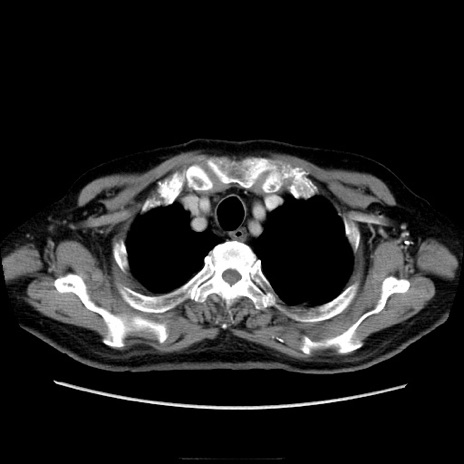

症例21(横断像)

【症例】70歳代男性

【主訴】腹痛

【現病歴】肝硬変・肝細胞癌にてかかりつけの方。約9時間前に食後より腹痛出現。症状が徐々に増悪し、嘔吐出現したため来院。

【既往歴】肝硬変、肝細胞癌(RFA、TACE後)

【身体所見】意識清明、表情苦悶様、BT 36℃、BP 129/78mmHg、P 88bpm、SpO2 97%(RA)、右上腹部から心窩部にかけて圧痛あり、反跳痛なし、筋性防御あり。

【データ】WBC 5800、CRP 0.16